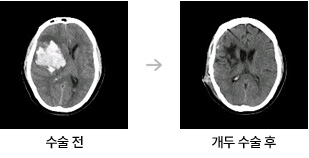

- 수술: 상황에 따라 출혈을 제거하고, 필요한 경우 뇌의 압력을 줄이기 위한 수술을 시행합니다.